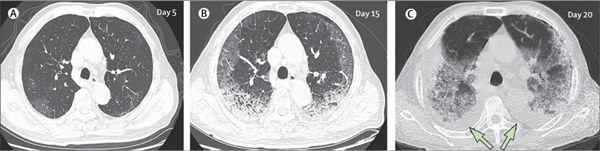

Đây là CT phổi của một bệnh nhân nam 77 tuổi (ở Trung Quốc) trong gần 3 tuần điều trị. Đáng tiếc, tình trạng của bệnh nhân nguy kịch, không qua khỏi do sức tàn phá mạnh của virus corona bên trong phổi. (A) - ngày thứ 5, sau khi khởi phát triệu chứng: các mảnh mờ đục bắt đầu loang lổ, ảnh hưởng đến nhu mô phổi hai bên, dưới màng cứng. (B) - ngày thứ 15, các đốm trắng hình lưỡi liềm đã chiếm lấy cả hai phổi, xuôi theo võng mạc phía sau và tập trung ở đáy. (C) - ngày 20, các tổn thương mở rộng ra hai bên phổi, đốm trắng gần như chiếm được cơ quan này và xuất hiện tình trạng tràn dịch màng phổi hai bên (mũi tên). 10 ngày sau lần quét này,bệnh nhân tử vong. Ảnh: The Lancet.